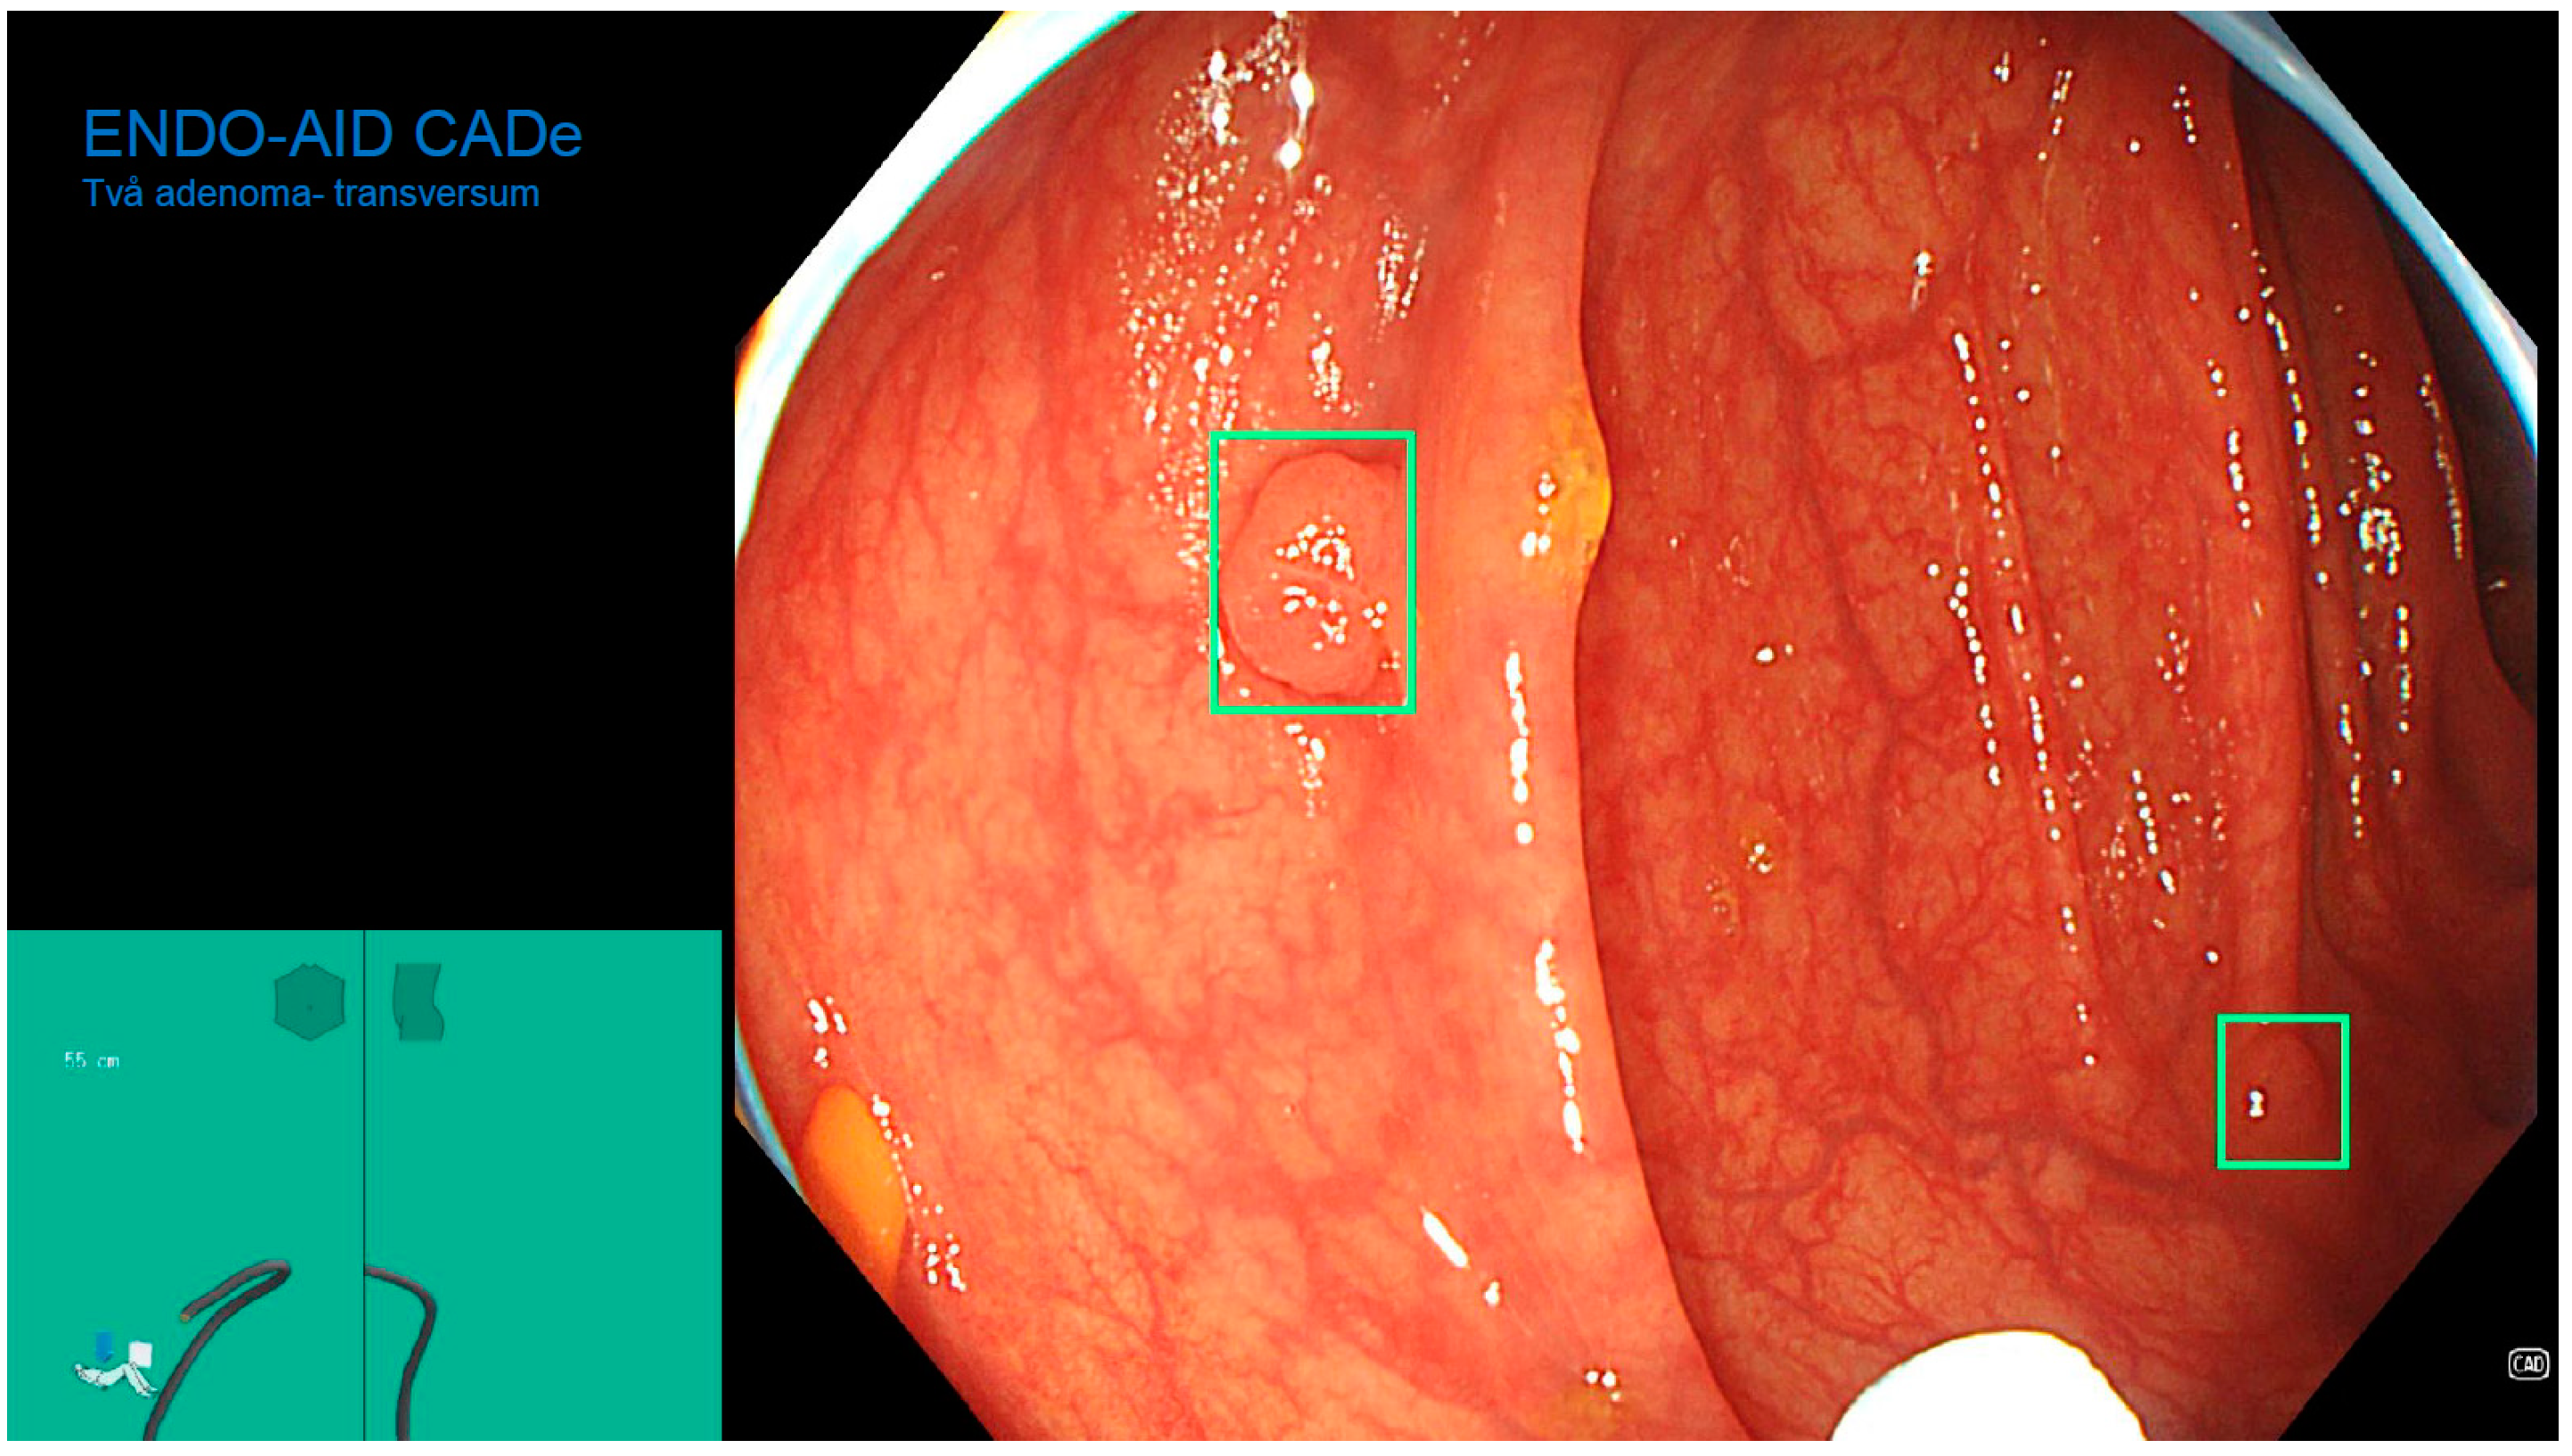

- Misawa, M.; Kudo, S.-E.; Mori, Y.; Cho, T.; Kataoka, S.; Yamauchi, A.; Ogawa, Y.; Maeda, Y.; Takeda, K.; Ichimasa, K.; et al. Artificial Intelligence-Assisted Polyp Detection for Colonoscopy: Initial Experience. Gastroenterology 2018, 154, 2027–2029. [Google Scholar] [CrossRef] [PubMed]

- Klare, P.; Sander, C.; Prinzen, M.; Haller, B.; Nowack, S.; Abdelhafez, M.; Poszler, A.; Brown, H.; Wilhelm, D.; Schmid, R.M.; et al. Automated polyp detection in the colorectum: A prospective study (with videos). Gastrointest. Endosc. 2019, 89, 576–582.e1. [Google Scholar] [CrossRef]

- Alagappan, M. Artificial intelligence in gastrointestinal endoscopy: The future is almost here. World J. Gastrointest. Endosc. 2018, 10, 239–249. [Google Scholar] [CrossRef]